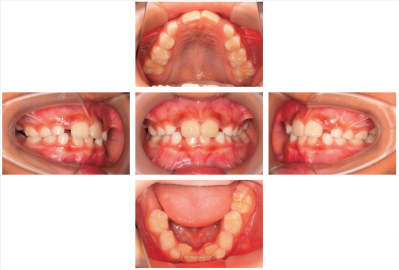

7歳の男児。歯の萌出遅延を近医で指摘され来院した。初診時の口腔内写真とエックス線写真を別に示す。

今後予想されるのはどれか。1つ選べ。

a. 上顎側切歯の高位

b. 下顎犬歯の早期萌出

c. 上顎右側第一大臼歯の挺出

d. 下顎右側第二大臼歯の遠心傾斜

e. 下顎右側第二乳臼歯の晩期残存